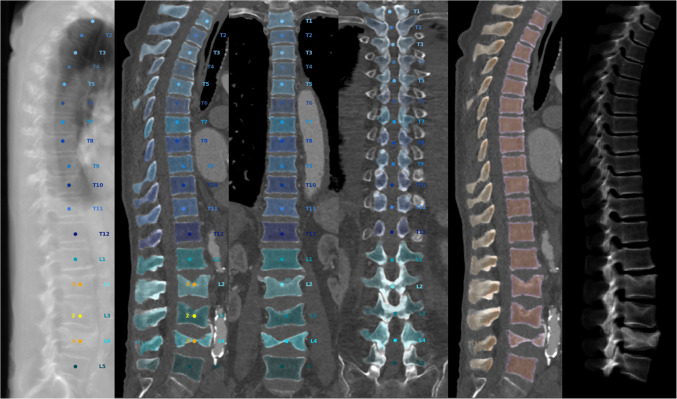

利用人工智能进行基于CT的机会性筛查发现,在计划经导管主动脉瓣置换术时获得的CT扫描中骨质疏松症的患病率很高(43%)。因此,机会性筛查可能是评估高危人群骨质疏松症的一种经济有效的方法。背景:骨质疏松症是一种与骨折和虚弱相关的未被诊断的疾病,但可以在常规计算机断层扫描(CT)中检测到。方法:采用基于人工智能(AI)的算法对207例经导管主动脉瓣置换术(TAVR)患者的临床常规胸腹CT扫描测量体积骨密度(vBMD)。结果:43%的患者有骨质疏松症(vBMD 3 L1-L3),且为老年人(83.0{四分位数间距[IQR]: 78.0-85.5} vs. 79.0{四分位数间距[IQR]: 71.8-84.0}年,p 3, p 3, p 0.05)。结论:应用基于人工智能的算法对TAVR计划CT扫描可显示高达43%的患者患有骨质疏松症。骨质疏松症可能是与TAVR患者虚弱和预后恶化相关的标志物。